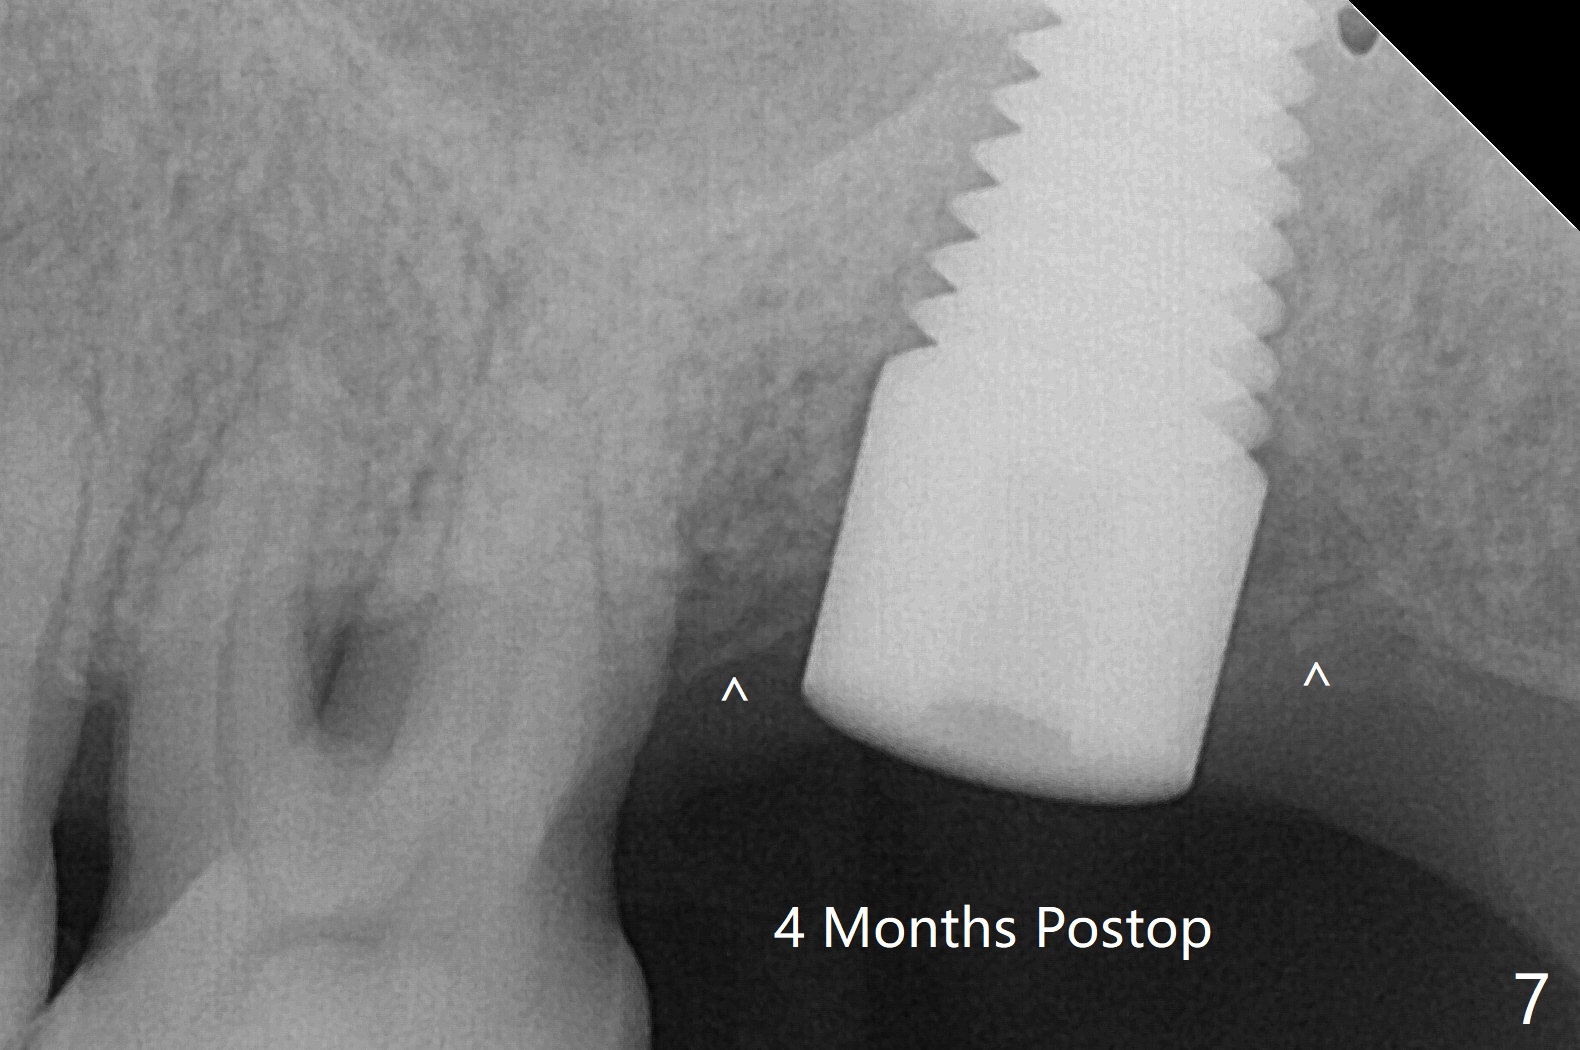

59岁男一年前因15号牙植牙周围炎去除牙冠和基台,植骨(图一:*(其实是第二次为周围炎植骨)),缝合。之后局部疼痛没有完全消失,准备再次手术(切开),如果螺纹暴露少,再次植骨。否则拔除植体(图二:黑色,手术探查的确不能挽救植体),之后有两个选择植骨(图三:灰色)或者即刻再次种植。由于原来植体比较粗(骨水平;6x12毫米),利用6(内径)/7(外径)毫米trephine drill和牙挺除去植体,留下相当大缺损(图二),植骨后(图三),位于缺损中间的骨粉(图四:棕色)可能因血供(红箭头)不足而愈合不佳。因此即刻重新种植显得有优势(图五(软组织水平植体,螺纹在自身骨(native bone)下)),让身体不必太辛苦(成骨)。放置5x5毫米基台目的是为树脂敷料提供固定点,以防PRF膜和缝线不能挽留粘性骨粉(*)。术后一个月撤除树脂敷料,伤口愈合正常(图六)。准备一个月后,制作临时牙冠。术后4个月取出5x5毫米基台,准备放置6x5毫米基台(图七),下面软组织水平植体没有疼痛或者松动,螺纹被骨粉或者再生骨质覆盖(^)。